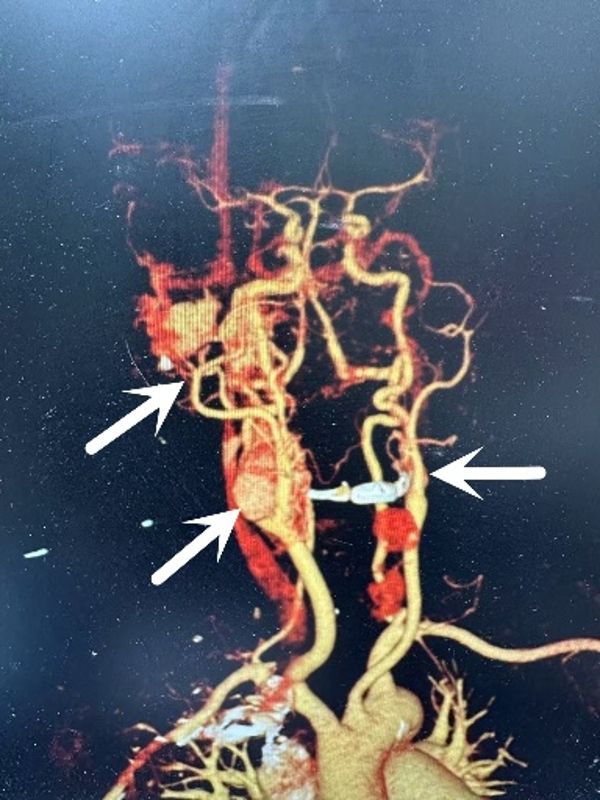

患者因咳嗽入住我院呼吸与危重症医学科,医生完善颅脑CT时发现肿瘤,请耳鼻咽喉头颈外科病院会诊后转入吴宝俊、李阳教授组。患者在耳鼻咽喉头颈外科病院进行进一步的检查,吴宝俊对肿瘤组织取活检病理,同时邀请相关科室会诊,最终各种检查及病理结果提示病人多发副神经节瘤:颈静脉球瘤+双侧颈动脉体瘤+中耳胆脂瘤。肿瘤较大且供血丰富,且包绕颈总动脉、颈外动脉,同时侵犯颅底岩骨段的颈内动脉,与后组颅神经关系密切,手术难度极大。

“副神经瘤多发更是极为罕见,即使在驰名世界的意大利皮亚琴察Gruppo Otologico 颅底中心,一年的手术也仅10例左右,在西北地区更是没有开展此类手术的先例。”西安交通大学第二附属医院耳鼻咽喉头颈外科病院主任任晓勇谈到,此类手术涉及颅底、颈部大血管,手术难度及风险极高,科室即刻进行重大疑难病例讨论(MDT),请相关科室及专家讨论手术实施方案及手术风险预防及处理措施。经会诊讨论后,决定行一期同侧颈静脉球切除术+颈动脉体瘤切除术+面神经-舌下神经吻合术。同时,医生做了充分的手术预案,如出现颈内动脉或其他大血管的损伤,则行覆膜支架。

手术中,耳科组教授吴宝俊、李阳主刀先行切除颈动脉体瘤,再行颈静脉球切除术+面神经-舌下神经吻合术,手术持续10余小时,在保留颈内动脉的基础上完整切除肿瘤,并保留后组颅神经功能。头颈组教授梁建民、盛颖协助,麻醉科李伟、薛丽教授保驾护航,手术室刘雄涛、李荣、邓睿、王旭斌等配合作。

术后第8天,患者出现颈部伤口隆起、出血。吴宝俊教授、李阳教授团队立即启动抢救预案,颈部压迫止血的同时,考虑到颈动脉假性动脉瘤破裂出血可能,联系介入室刘强主任行右侧颈动脉血管造影检查,见右侧大脑侧支循环已经建立,行右侧颈动脉结扎。当天,患者生命体征平稳,无身体偏瘫,面神经功能恢复好。目前,患者已痊愈出院。